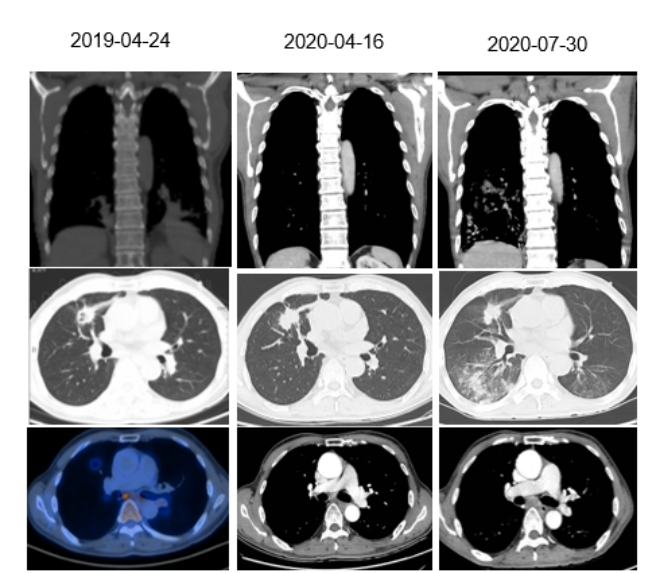

2019年04月24日于院外影像诊断中心行PET-CT示:1、右肺中叶分叶状结节,代谢活跃,考虑为肺癌;纵隔内(上、下气管旁、主动脉弓下、隆突下)及双肺门多发淋巴结代谢活跃,考虑转移;全身多处骨骼破坏代谢活跃,考虑转移。2、双肺下叶大片状斑片模糊影,代谢活跃,考虑为感染性病变,建议治疗后复查;双肺胸膜下多发炎性小结节。

2020年4月胸部CT复查提示肺部病灶稳定,MR发现新发脑转移,患者继续口服奥希替尼。直至2020年8月,患者停服奥希替尼,并接受2周期的化疗,方案为培美曲塞+卡铂+贝伐珠单抗。